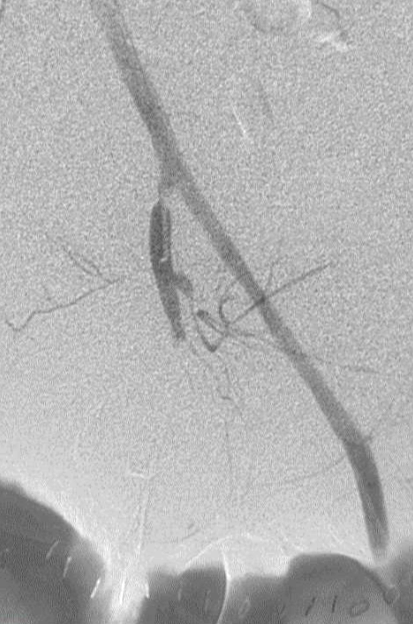

所有年龄超过 40 岁的患者, 卵巢受损 14%-43% 研究中闭经发生率(15%)与单纯UAE报告相似,可能与患者年龄(≥45岁)及卵巢储备自然下降有关。 ![]() 50岁,长期因子宫肌瘤导致月经出血过多,痛经和贫血。 子宫肌瘤栓塞术前,显示双侧子宫动脉发育不全,子宫肌瘤双侧卵巢动脉。 经皮股动脉穿刺双侧卵巢动脉栓塞,先500μm-700μm emboSphere 微球 术后4周,和6月的中短期随访,月经正常,子宫容积减少,贫血纠正,无卵巢功能衰竭。但看起来非灌注容积较少。 术后9月,由于子宫肌瘤持续存在,患者自己希望绝经,行全子宫和双侧卵巢切除术 术后病理,子宫内可见栓塞微粒伴有坏死,卵巢内也见栓塞微粒,但卵巢功能未受损。